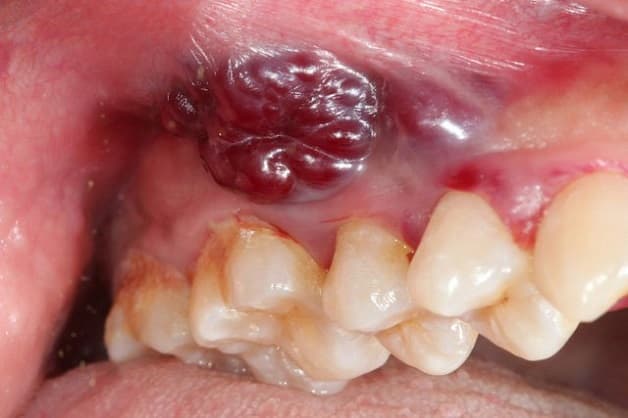

1.3 Răng sưng hoặc chảy mủ

Khi kiểm tra xung quanh chiếc răng đau, vùng nướu có tình trạng đỏ, sưng, thậm chí có thể thấy mụn mọc trên khu vực nướu răng gần chiếc răng đang bị nhiễm trùng và sát chân răng. Thêm vào đó, mủ trắng cũng có thể xuất hiện ở chỗ đau hoặc xung quanh chiếc răng, các cơn đau sẽ giảm khi mủ bắt đầu chảy ra.

Kèm theo hiện tượng chảy mủ là hơi thở hôi, có mùi khó chịu do sự tích tụ mủ bên trong khoang miệng. Trường hợp răng bị nhiễm trùng nghiêm trọng, mủ sẽ chảy ra từ răng hoặc từ nốt mụn, có thể xảy ra bất ngờ khi ổ áp xe bị vỡ.